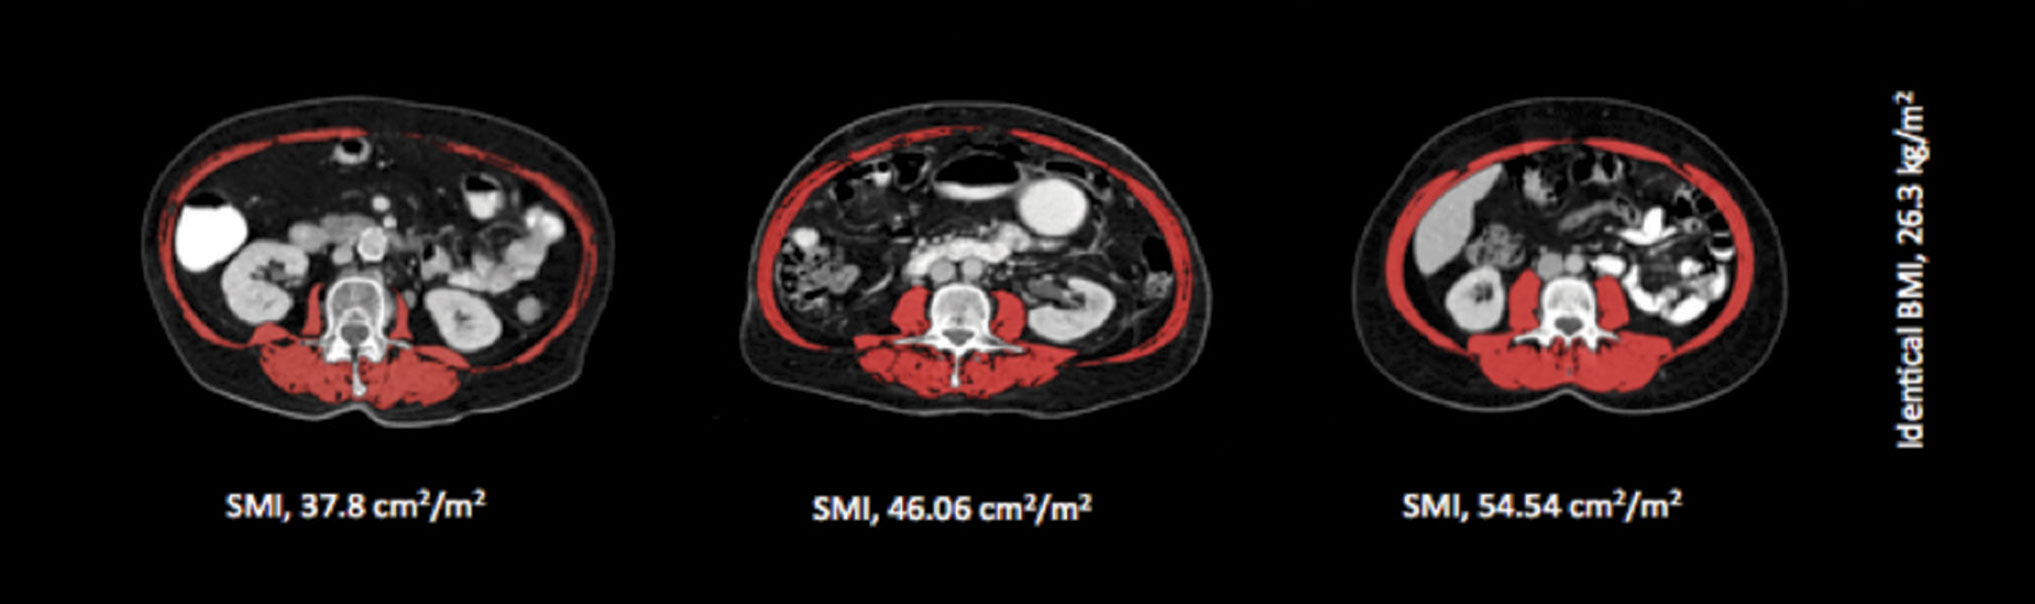

Figure 1A. Shows the variation in fat mass and body mass index (BMI) for four males with identical amounts of skeletal muscle

Figure 1A. Shows the variation in fat mass and body mass index (BMI) for four males with identical amounts of skeletal muscle(click to enlarge)

While the majority of cancer patients present with involuntary weight loss at the time of diagnosis,2 in the era of obesity cancer patients may not ‘look’ malnourished, with recent studies reporting that 40-60% are overweight or obese, even in the setting of metastatic disease.2,22,23,24 As the most clinically relevant phenotypic feature of cancer cachexia is muscle loss, identifying those with muscle loss becomes a huge challenge in overweight and obese patients as the loss of muscle is masked by excessive adiposity.

Sarcopenia

Sarcopenia comes from the Greek ‘sarx’ for flesh and ‘penia’ for loss, and is defined as ‘the age-associated loss of skeletal muscle mass and function’, often described as a muscle mass two standard deviations below normal.25 The best way to diagnose sarcopenia is by direct measurement of lean mass by DXA or CT. Despite the presence of high BMI in cancer patients, sarcopenia is present in 20-70% depending on the tumour type. Cancer patients with sarcopenia have a poor prognosis regardless of overall body weight.24 Recently it has emerged that the co-existence of obesity and sarcopenia is the worst-case scenario.26

As discussed previously, an additional challenge for cancer care providers is the fact that sarcopenia is a phenomenon that may be obscured within the bulk of body weight and body weight change and this is now recognised as a clinically important phenomenon.

Levels of malnutrition in 2015 are similar to those reported  more than 35 years ago, but today less than 7% of cancer patients are underweight (BMI < 18.5 kg/m2). The majority ‘look’ normal and 40-63% are overweight or obese. However, cachexia and sarcopenia are highly prevalent across all BMI categories with approximately one-third of obese cancer patients meeting the criteria for cachexia and 17-19% meeting criteria for sarcopenia. Cachexia and sarcopenia impact significantly on patients’ quality of life, tolerance to chemotherapy and survival.